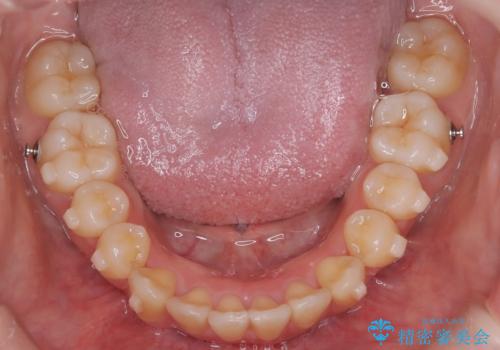

【インビザライン】アンカースクリューを用いた遠心移動

- 前歯の突出を主訴に来院されました。

アンカースクリューとインビザラインを用いて遠心移動を行うことでできる限り前歯を下げて叢生の改善を行いました。

遠心移動を行う際は、患者様にゴムの使用をお願いしております。